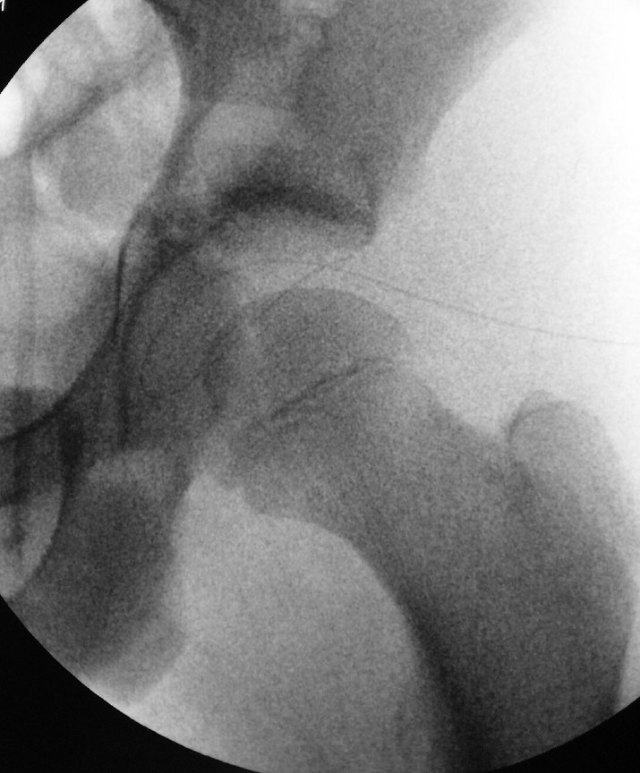

The joint is thoroughly irrigated with fluid to wash out the bacteria and pus.

Any infected tissue inside the joint can be debrided with an arthroscopic shaver.

A drain is inserted into the left hip joint to allow drainage for the next few days. It can be removed in the ward once the infection is under control.